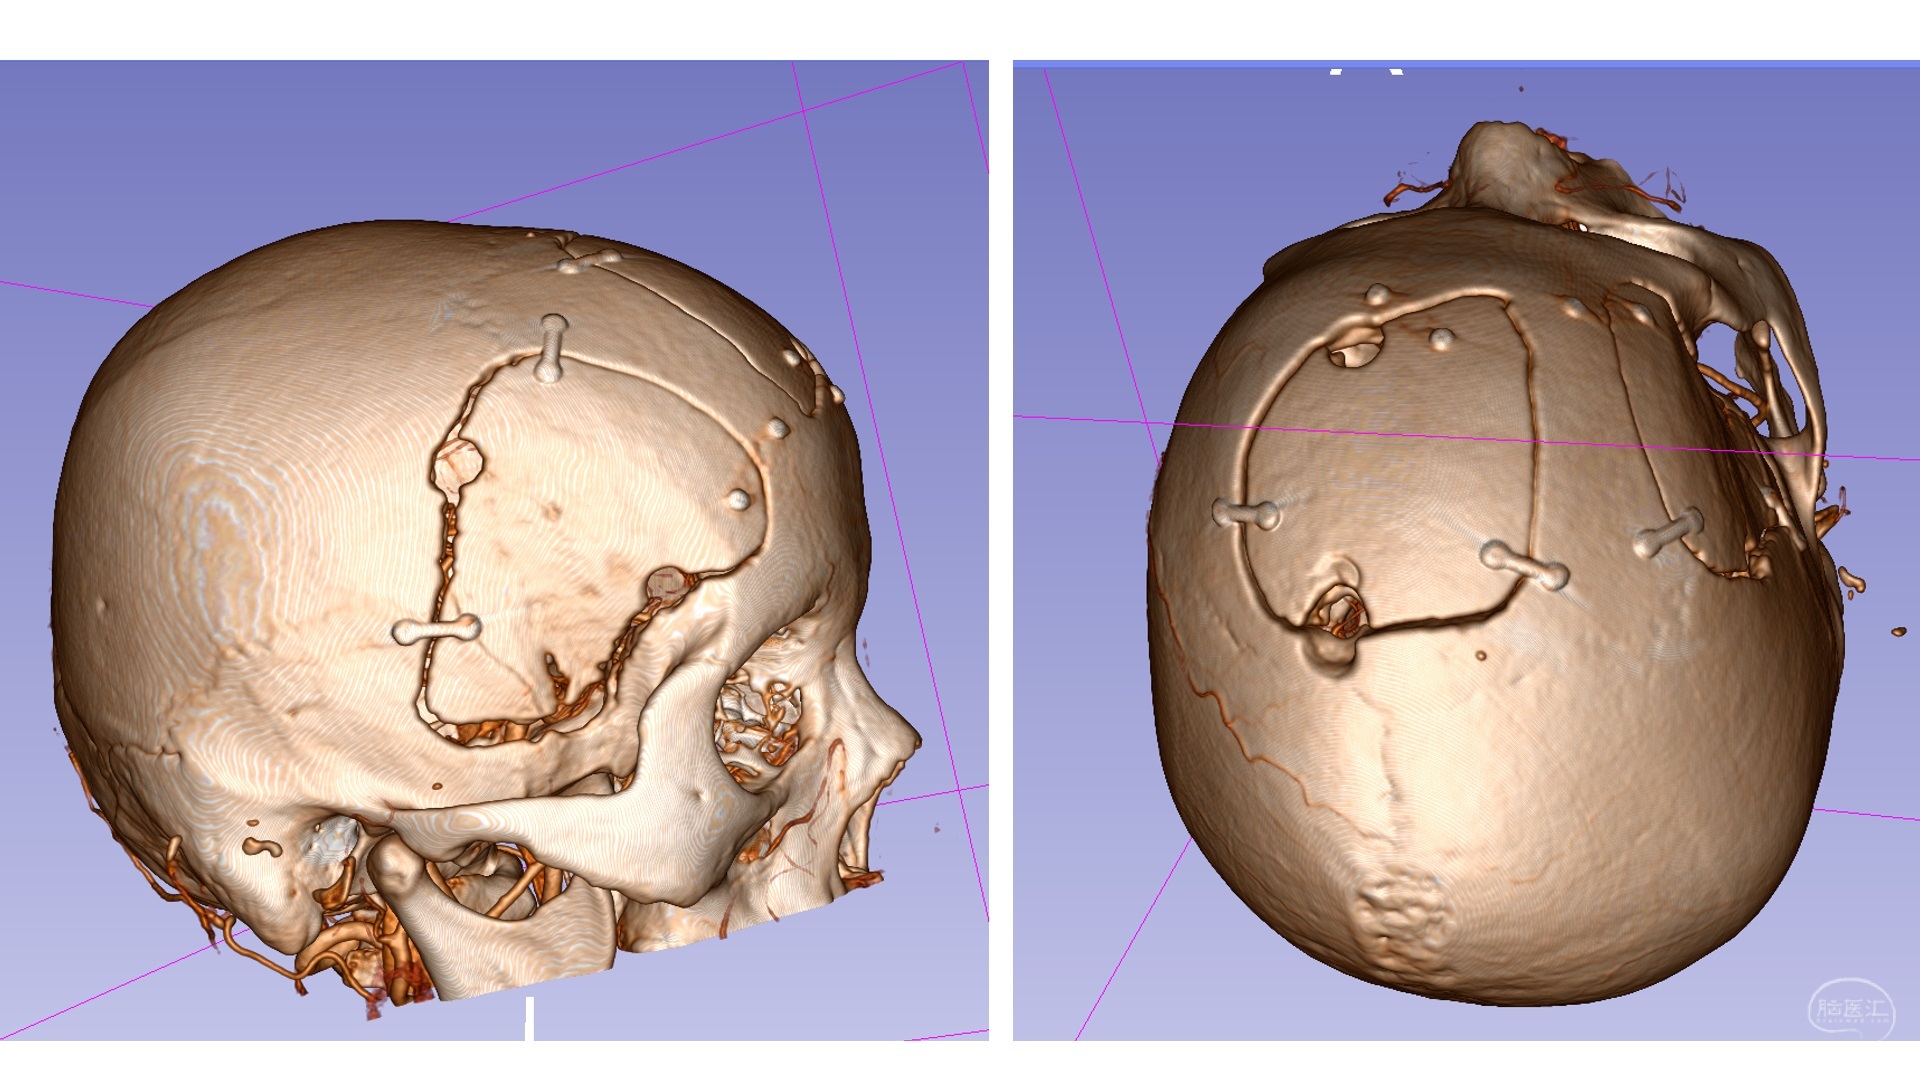

手术切口及骨瓣设计如图所示:右侧翼点联合中线经纵裂入路。

骨窗:由于考虑有可能处理可疑的后交通动脉瘤,翼点的骨窗更靠中颅底。